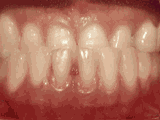

Patient's underbite was causing her to have jaw joint discomfort and excessive wear patterns on her teeth. After thirty months of treatment starting at age thirty-two, she now finds smiling and chewing much easier.